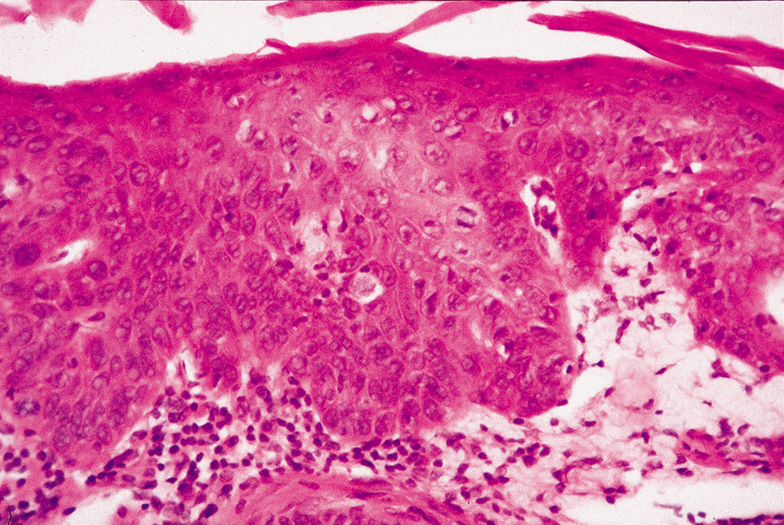

Histologically, the epidermis is replaced by an atypical proliferation of keratinocytes showing nuclear hyperchromatism and pleomorphism. There are many dyskeratotic cells and mitotic figures, some of which may be atypical (Fig. 43). The overlying stratum corneum is parakeratotic. If occurring on sun-exposed skin, there will be solar elastosis.

Fig. 43. Carcinoma In Situ—A. Low-power photomicrograph demonstrating parakeratosis, hyperkeratosis, and epithelial dysplasia confined to the epithelium. No invasion is present. B. High-power photomicrograph revealing pleomorphic cells and active mitosis (hematoxylin and eosin stain). (Photos courtesy of William Morris, M.D.)